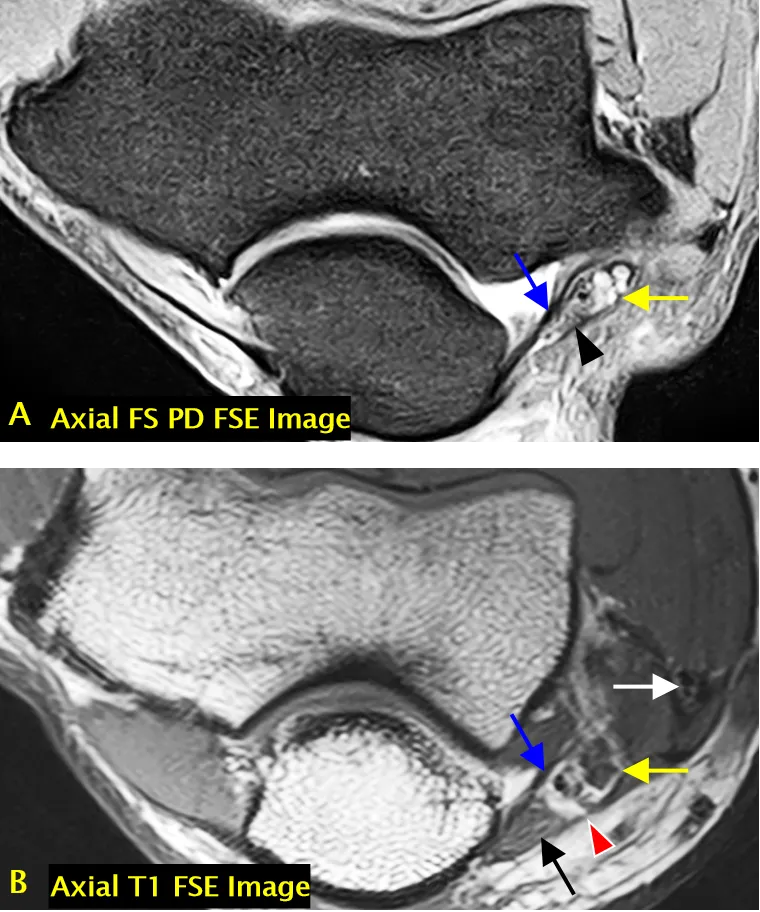

尺神经(黄色箭头标注);可见肱三头肌(长头)(A 中白色箭头标注)、指深屈肌(C 中黑色标注)、尺侧腕屈肌(肱骨头)(C 中白色标注)、尺侧腕屈肌(尺骨头)(C 中黄色标注)、尺侧腕屈肌(D 中红色标注)、指浅屈肌(C、D 中蓝色 * 标注);ME = 内上髁,OP = 鹰嘴

尺神经沟(骨纤维通道)结构

• 尺神经沟的底部由内侧副韧带后束和关节囊构成。

• 尺神经沟的顶部由尺神经沟支持带和尺侧腕屈肌筋膜深层(弓状韧带)构成。

内侧副韧带后束(蓝色箭头标注)、尺神经沟支持带(A 中箭头头标注)、弓状韧带(B 中箭头头标注)、尺神经(黄色箭头标注);可见尺侧腕屈肌(B 中黑色箭头标注)和共同屈肌肌腱(B 中白色箭头标注)。